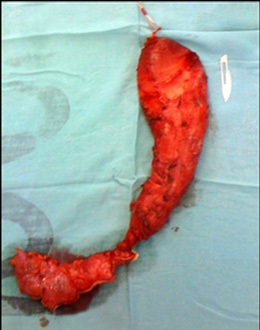

In the period between March 2008 and December 2021, 7 patients were treated minimally invasively for presenting mega esophagus due to achalasia at the end of stage (Figure 1).

Of the total, 3 corresponded to the male sex and 4 to the female sex. The average age was 54.7 with a range of 35 to 66 years. One case corresponded to a megaesophagus of Chagasic origin, and the other 6 cases were due to recurrence of the Heller-Dor myotomy, which was treated with endoscopic dilations. The treatments performed were: 1 laparoscopic transhiatal esophagectomy and a minimally invasive esophagectomy in the prone position (Figure 2) 4 esophagus ardioplasty procedures, as described in Figure 3, and 1 case of resection of the esophagogastric junction and Roux-en-Y bypass.

Figure 1: Esophagus barium swallow.